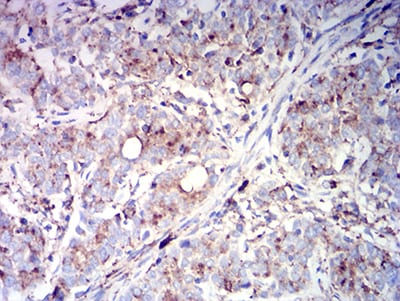

分类: 科研抗体货号: 31424别名: MLA1; ME491; LAMP-3; OMA81H; TSPAN30应用: IHC,FCM反应种属: Human

分类: 科研抗体货号: 31423别名: MLA1; ME491; LAMP-3; OMA81H; TSPAN30应用: IHC,FCM反应种属: Human